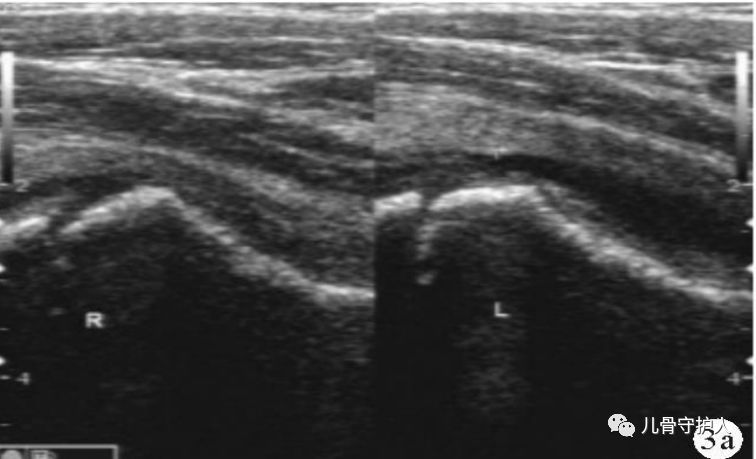

4.X:骨盆轻度倾斜,髋关节囊肿胀,关节间隙增宽,无骨质破坏。B超:患髋股骨颈颈前间隙增宽,双侧差值大于1mm。滑膜增厚,关节积液。